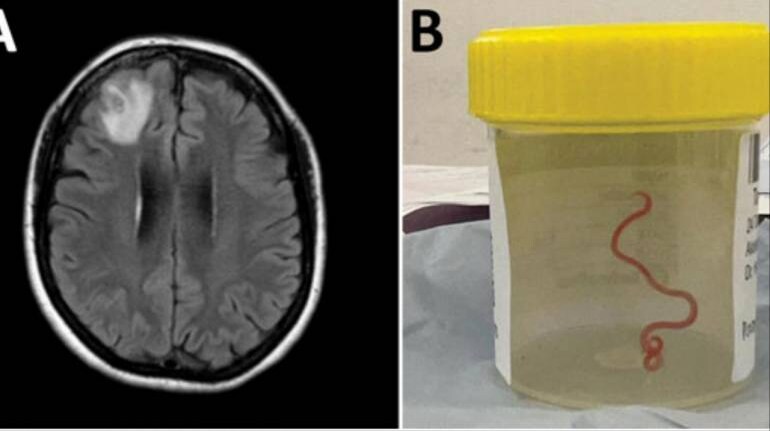

Doctors in Australia found a live worm living inside a woman's brain (Image credit: Centres for Disease Control and Prevention)

However, by 2022, her symptoms evolved to depression and forgetfulness. She was referred to Canberra hospital, where an MRI scan led to the discovery of the live worm in the right frontal lobe lesion of her brain.

“Canberra is a small place, so we sent the worm, which was still alive, straight to the laboratory of a CSIRO scientist who is very experienced with parasites,” Senanayake said. “He just looked at it and said, ‘Oh my goodness, this is Ophidascaris robertsi’.”

Ophidascaris robertsi is a roundworm typically found in pythons. Doctors are not sure how it found its way to the woman’s brain, although they think she might have eaten grass tainted by the snake’s faeces. The woman lives in an area where carpet pythons are common and often collects native grasses to use in cooking.